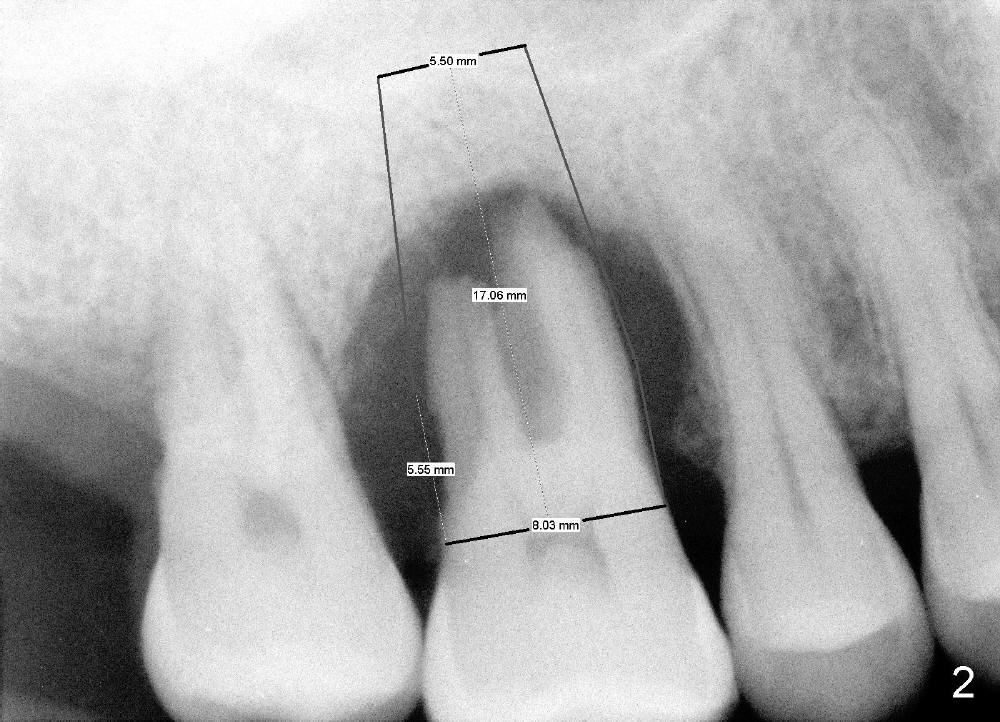

The upper right 1st molar of a 48-year-old man has severe perio endo disease (Fig.1 #3); the bone height for immediate implant (Fig.2) is about 3.5 mm (Fig.1 vertical line). There is a buccal (Fig.3 B) abscess (*); the palatal (Fig.4 P) root is exposed. After extraction, the socket available for immediate implant (Fig.5,6 S) is buccal (without septum), whereas the apex of the palatal root is far away from the main socket. In fact there is an advantage: the socket is smaller. Osteotomy is created in the main socket as palatal as possible, using osteotomes, reamers and taps (Fig.7 T). The sinus floor is lifted (Fig.7 ^). When 7x17 mm implant is placed (Fig.8 I), the insertion torque is >60 Ncm. The remaining socket (Fig.8 *) is to be packed with mixture of autogenous bone, allograft and synthetic bone (Osteogen) (Fig.9,10 <). Immediate insertion of an abutment (Fig.8-10 A) helps retain perio dressing (Fig.11,12). No collagen membrane is used in this case to cover the bone graft before placement of perio dressing. Postop the patient cannot tolerate oral Amoxicillin because of stomach upset. The dose is reduced. Two weeks postop, the perio dressing is stable, but discolors (Fig.13). When the dressing is removed, the buccal bone graft is exposed, which is not abnormal. What is unusual is discoloration (Fig.14). The significance of the latter is not revealed until 3 months postop when the patient remains asymptomatic, but there is an apical fistula (Fig.15 <). There is a communication between the fistula and the buccal sulcus of the implant: water passing freely. Based on the position of the buccal plate of the neighboring teeth (*), the buccal plate of the implant should be lost, which is consistent with finding of PA (Fig.16, as compared to Fig.8). Guided bone regeneration seems necessary.